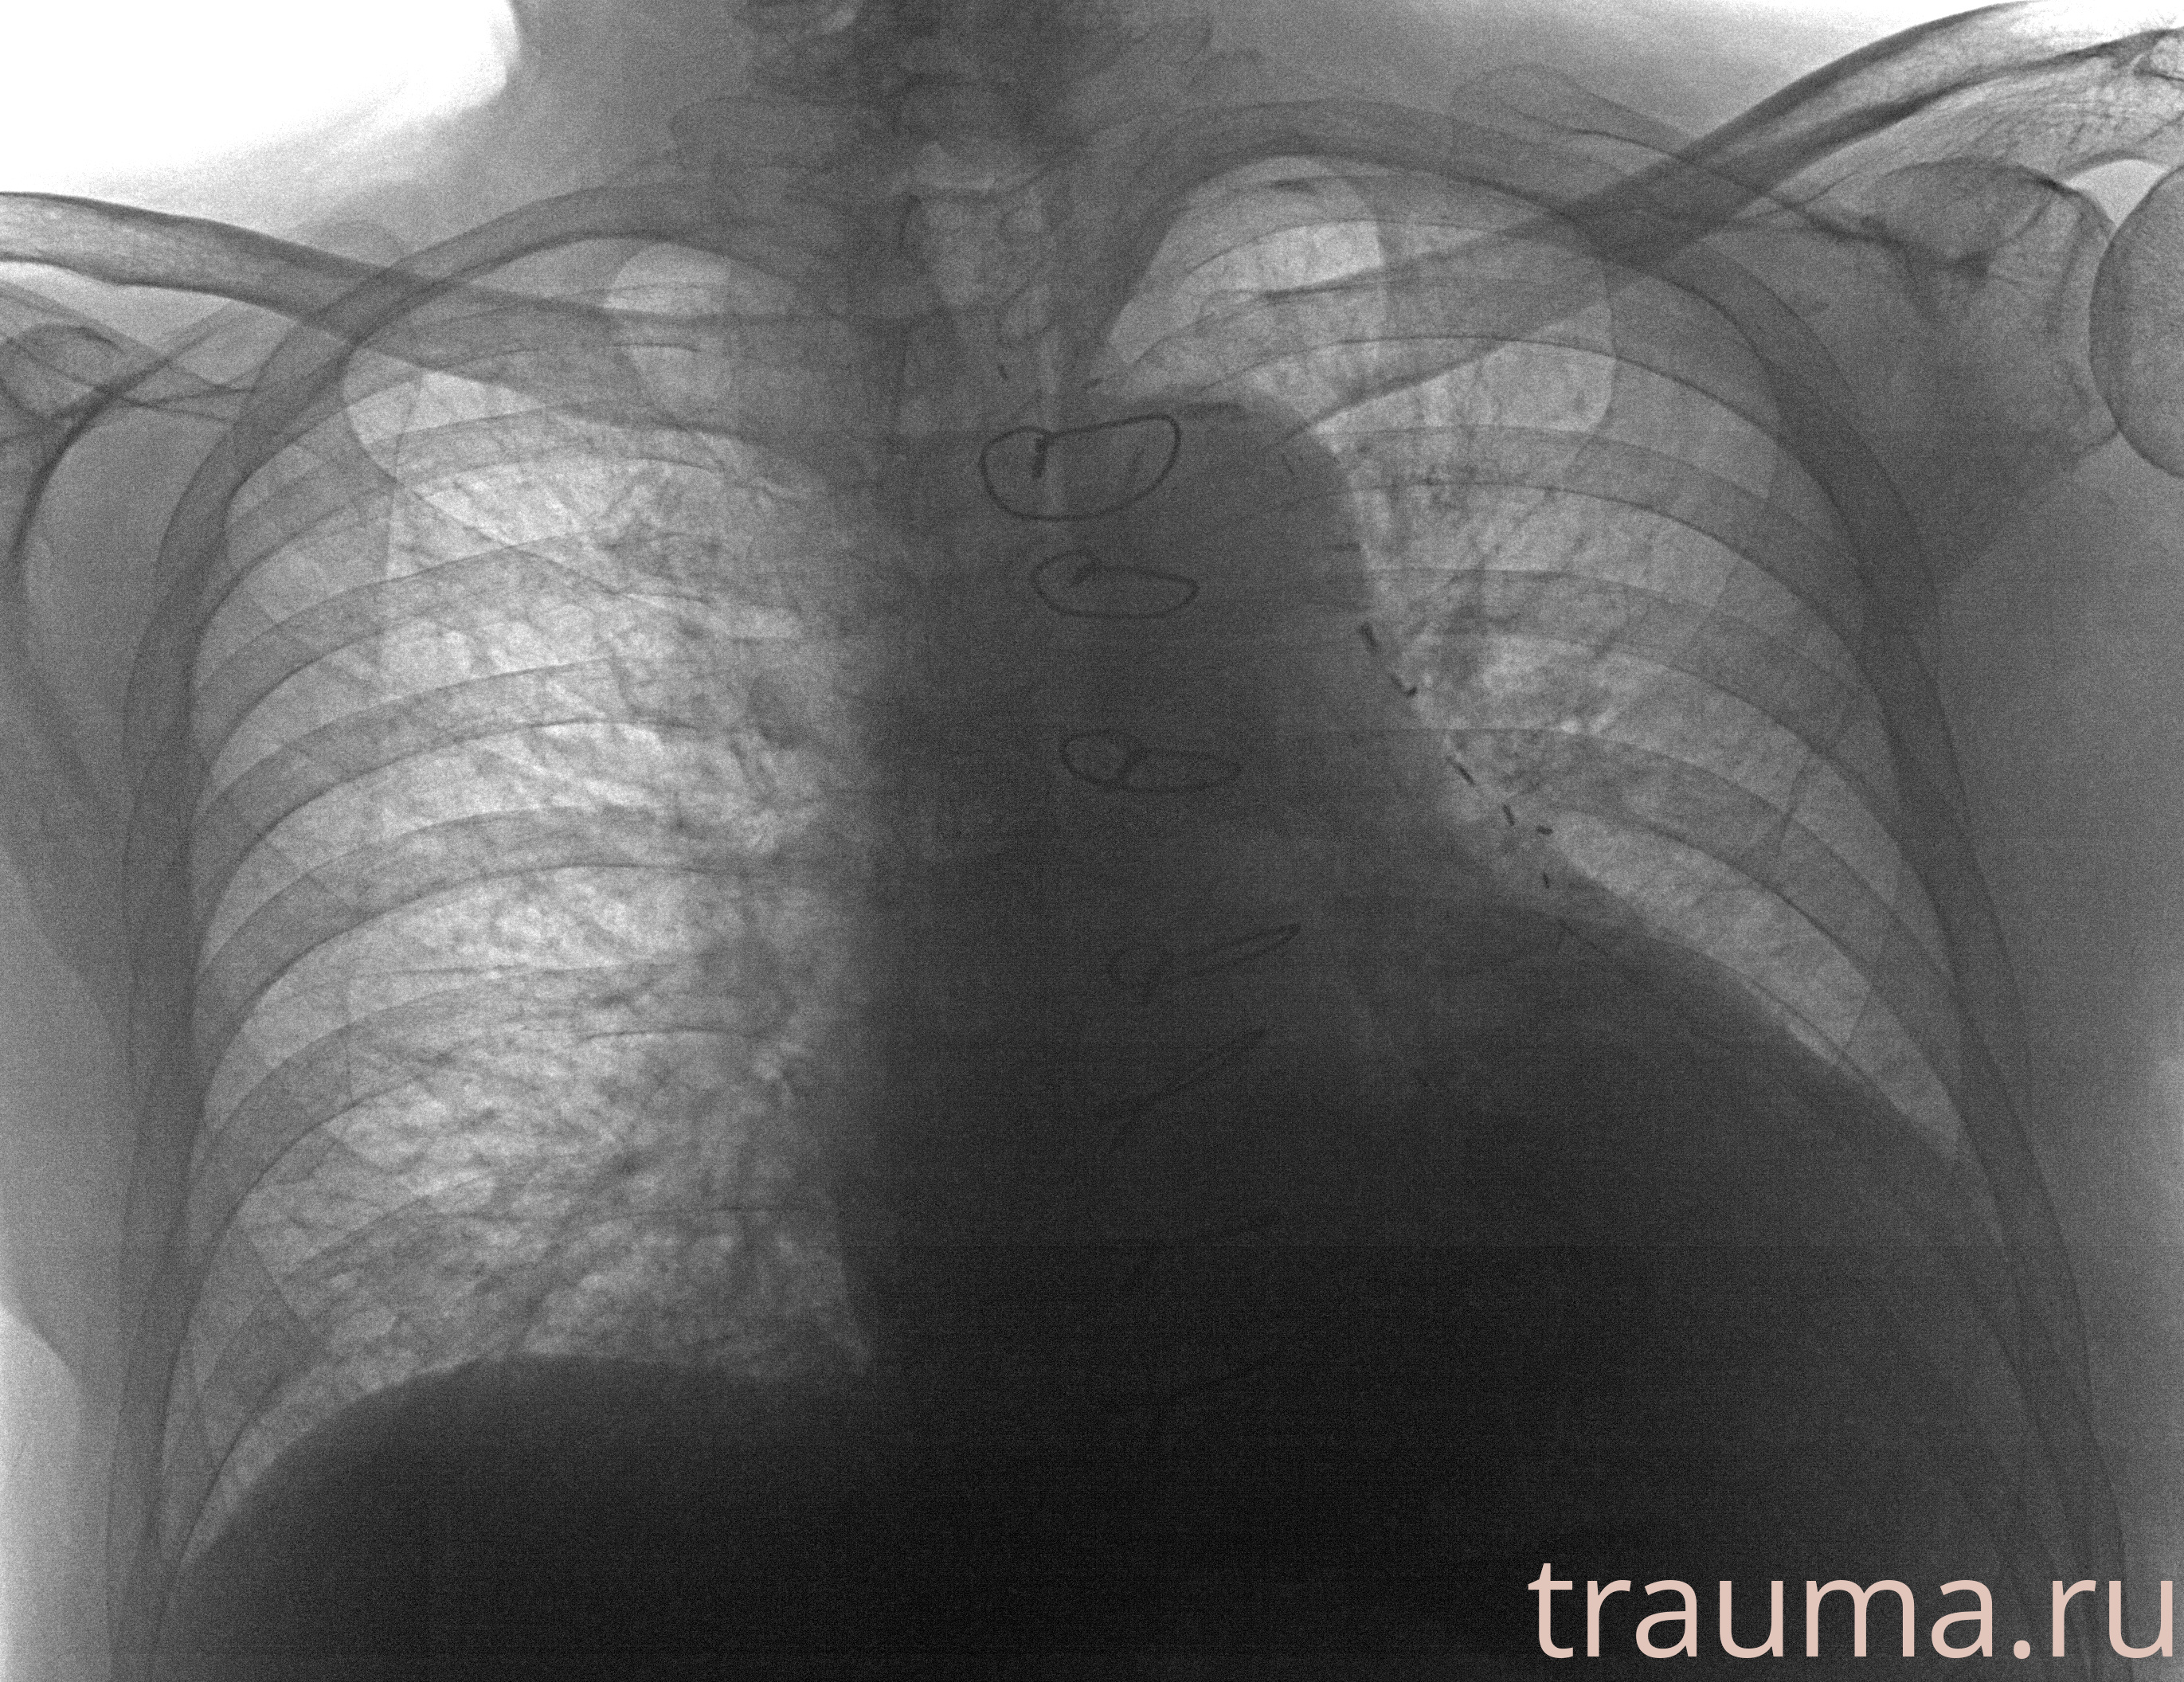

Рентген на дому: по вашему адресу приезжает врач-рентгенолог, травматолог-ортопед с мобильным рентгеновским аппаратом, проводит диагностику травмы или заболевания, делает необходимые рентгенограммы, дает рекомендации по дальнейшему лечению. Получить качественные снимки в домашних условиях возможно благодаря уникальной методике, разработанной МосРентген Центром для института  Склифосовского